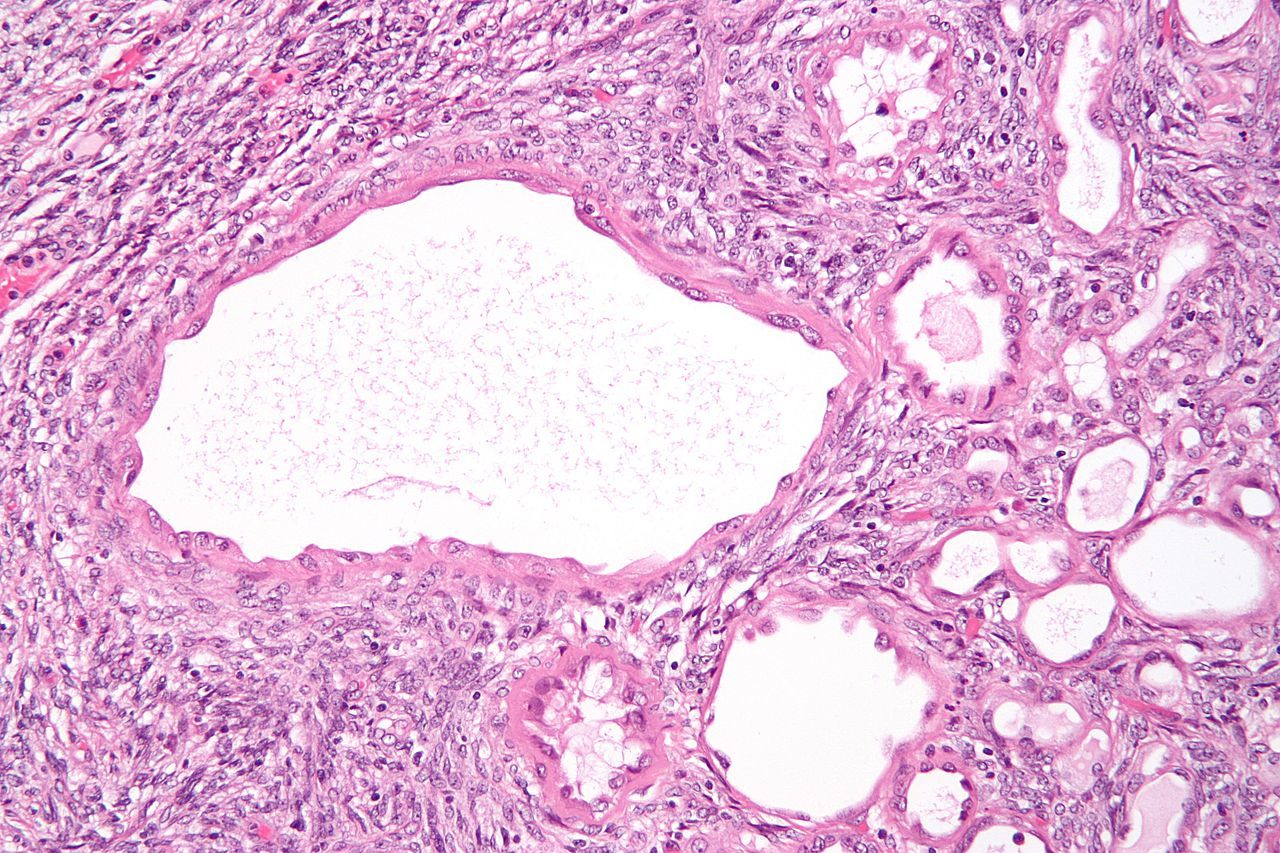

Tubulocystic renal cell carcinoma

Tumor consisting of a spongy collection of dilated tubules lined by plump, pink, apocrine-looking cells with round nuclei. Best described as “a spongy collection of dilated tubules lined by fat pink apocrine cells.”

Described as a “softy, creamy mass” on gross pathology.